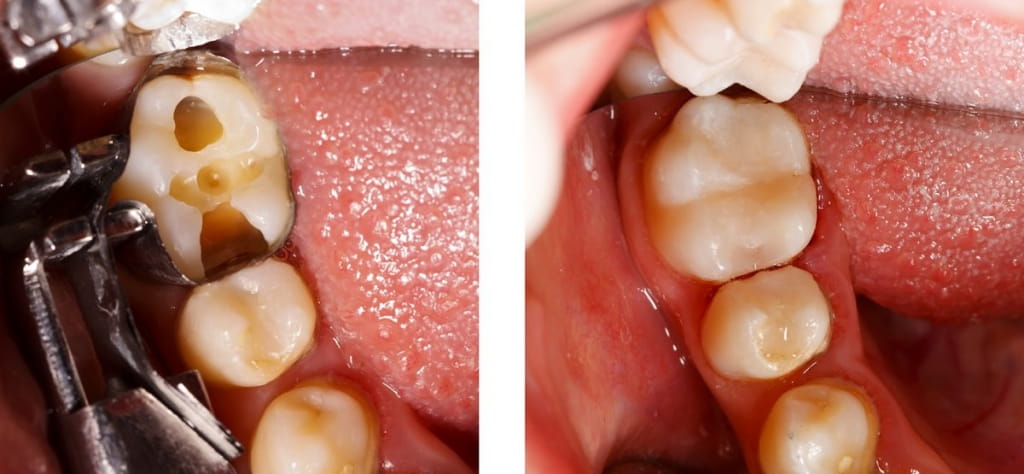

White Fillings

We use fillings to replace and restore your tooth structure damaged due to decay or fracture. But gone are the days of a mouth filled with metallic fillings. We use state-of-the-art, tooth-colored resin or porcelain materials to fill the hole or fracture, eliminating unsightly and unhealthy silver/mercury fillings and giving you a more natural looking smile.